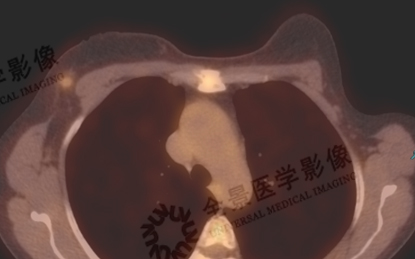

一站式检查可采集到多设备影像数据,并对数据按照同一体位和床位进行融合分析,为医生的准确诊断提供了扎实的信息基础。

列举了我中心基于一站式扫描的影像融合案例。如乳腺结节定性,乳腺微小病灶检出及定性,浸润性导管癌分期,浸润性导管癌与乳腺纤维瘤良恶性鉴别等。

案例展示: